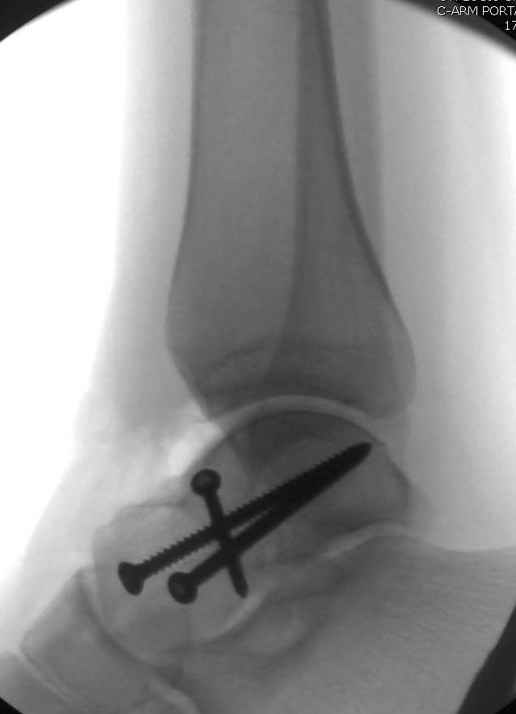

Для доступа к задне-медиальному суставному фрагменту я выполнил косую остеотомию внутренней лодыжки у её основания -получается хороший доступ к голеностопу, адекватный обзор и возможность восстановить суставную поверхность. фрагмент фиксировал двумя 3,5 мм спонгиозными винтами с неполной резьбой, *утопив* головки винтов в кость. Аналогичная фиксация и двумя тягловыми винтами и внутренней лодыжки. \в качестве альтернативы для

фиксации фрагмента тарана можно было бы использовать и герберт винты, но по организационным причинам :-(( набора не оказалось под рукой).

Вдогонку по поводу перелома таранной кости, больная 81, не страдает диабетом, перелом закрытый, в первый же день поступления ограничились временным наружным фиксатором (как на снимке).